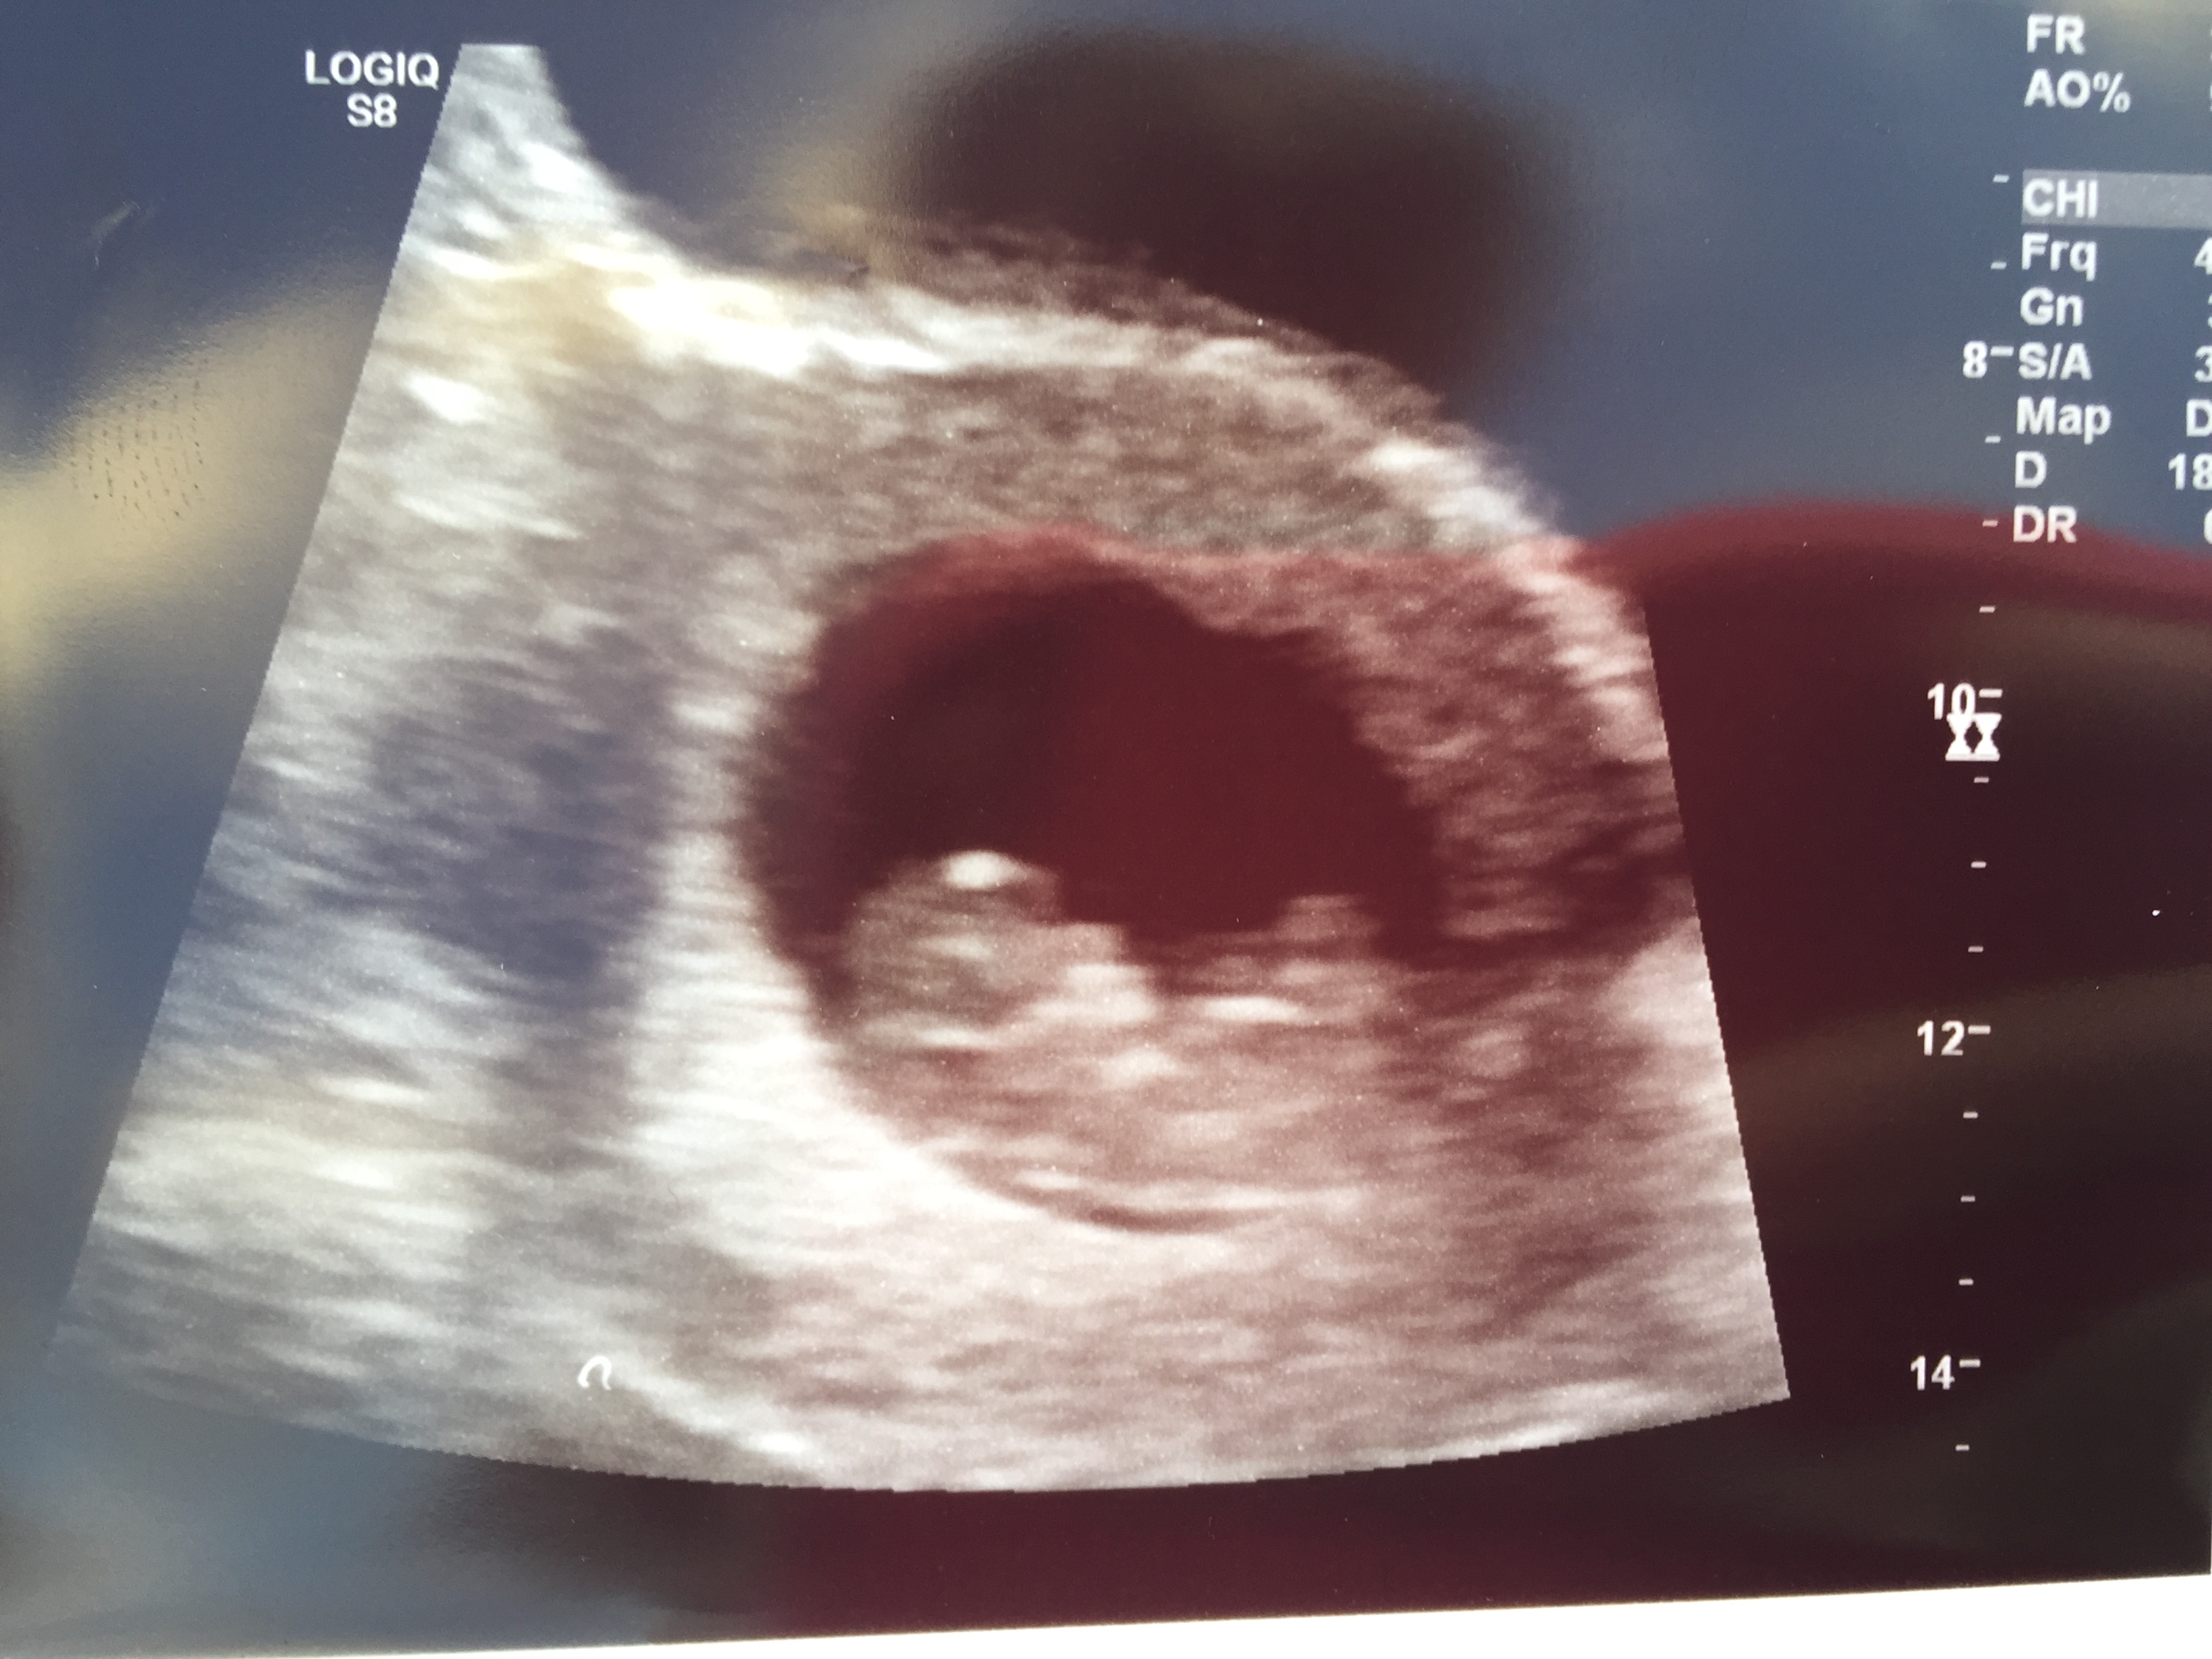

• So, my little cupcake looks like an absolute alien. The tech said that the part that looks like alien eyes is not the face. She said the part at the opposite end is the back of the head. Anybody know exactly what Im looking at here? This is a 12 almost 13 week scan.